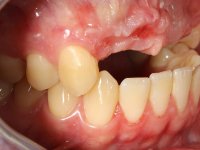

Paciente do sexo masculino, com 22 anos de idade e não fumador. Apresentou-se na consulta 6 meses após um acidente de viação em que perdeu os dentes 21, 22, 23 e 24. Os dentes 12 e 11 apresentavam mobilidade grau 3 apresentando-se também com extracção indicada. A arquitectura gengival da zona desdentada apresentava-se retraída e planificada.

O paciente foi observado conjuntamente e a dúvida que surgiu de imediato foi se seria possível com a regeneração óssea a efectuar poder ser reabilitada naturalmente a zona das papilas interdentárias. Nesse sentido foi feito um enceramento de diagnóstico que contemplaria as duas hipóteses, utilizando ou não a cerâmica gengival. A confecção desse enceramento foi fundamental para expor ao paciente a dificuldade da reabilitação. O wax-up deu origem a um mock-up que foi aprovado pelo paciente e que simultaneamente serviu de guia imagiológica. O caso foi planificado cirurgicamente e realizada uma guia cirúrgica com que foram colocados os implantes. Após 10 semanas foi feita a 1ª impressão para confecção da ponte provisória. Foram criados os primeiros perfis de emergência na gengiva artificial e foi digitalizado o modelo. Por processo de CAD-CAM foi confeccionada uma ponte provisória aparafusada baseada no enceramento de diagnóstico. A ponte trabalhou durante 8 semanas os tecidos moles que foram fielmente copiados numa impressão com técnica de moldeira aberta. Os transferes foram individualizados com resina composta para copiarem fielmente os perfis de emergência criados pela ponte provisória. Confeccionado o modelo de trabalho definitivo, foi realizada uma infra-estrutura em zircónio seguindo a orientação do enceramento de diagnóstico. O assentamento da infra-estrutura foi testado em boca e simultaneamente foi novamente impressionados os tecidos moles com um silicone fluido. Nessa consulta foi feito o levantamento da cor. Os dentes 13 e 23 apresentavam uma saturação anormalmente forte que resolvemos não valorizar, optando por privilegiar a relação com o sector antero-inferior. Foi realizada uma nova gengiva artificial com a impressão que acompanhou a impressão de arrasto com a infra-estrutura. Após a colocação da cerâmica na infra-estrutura foram coladas as meso-estruturas. O trabalho final foi aparafusado lentamente permitindo a adaptação dos tecidos moles.